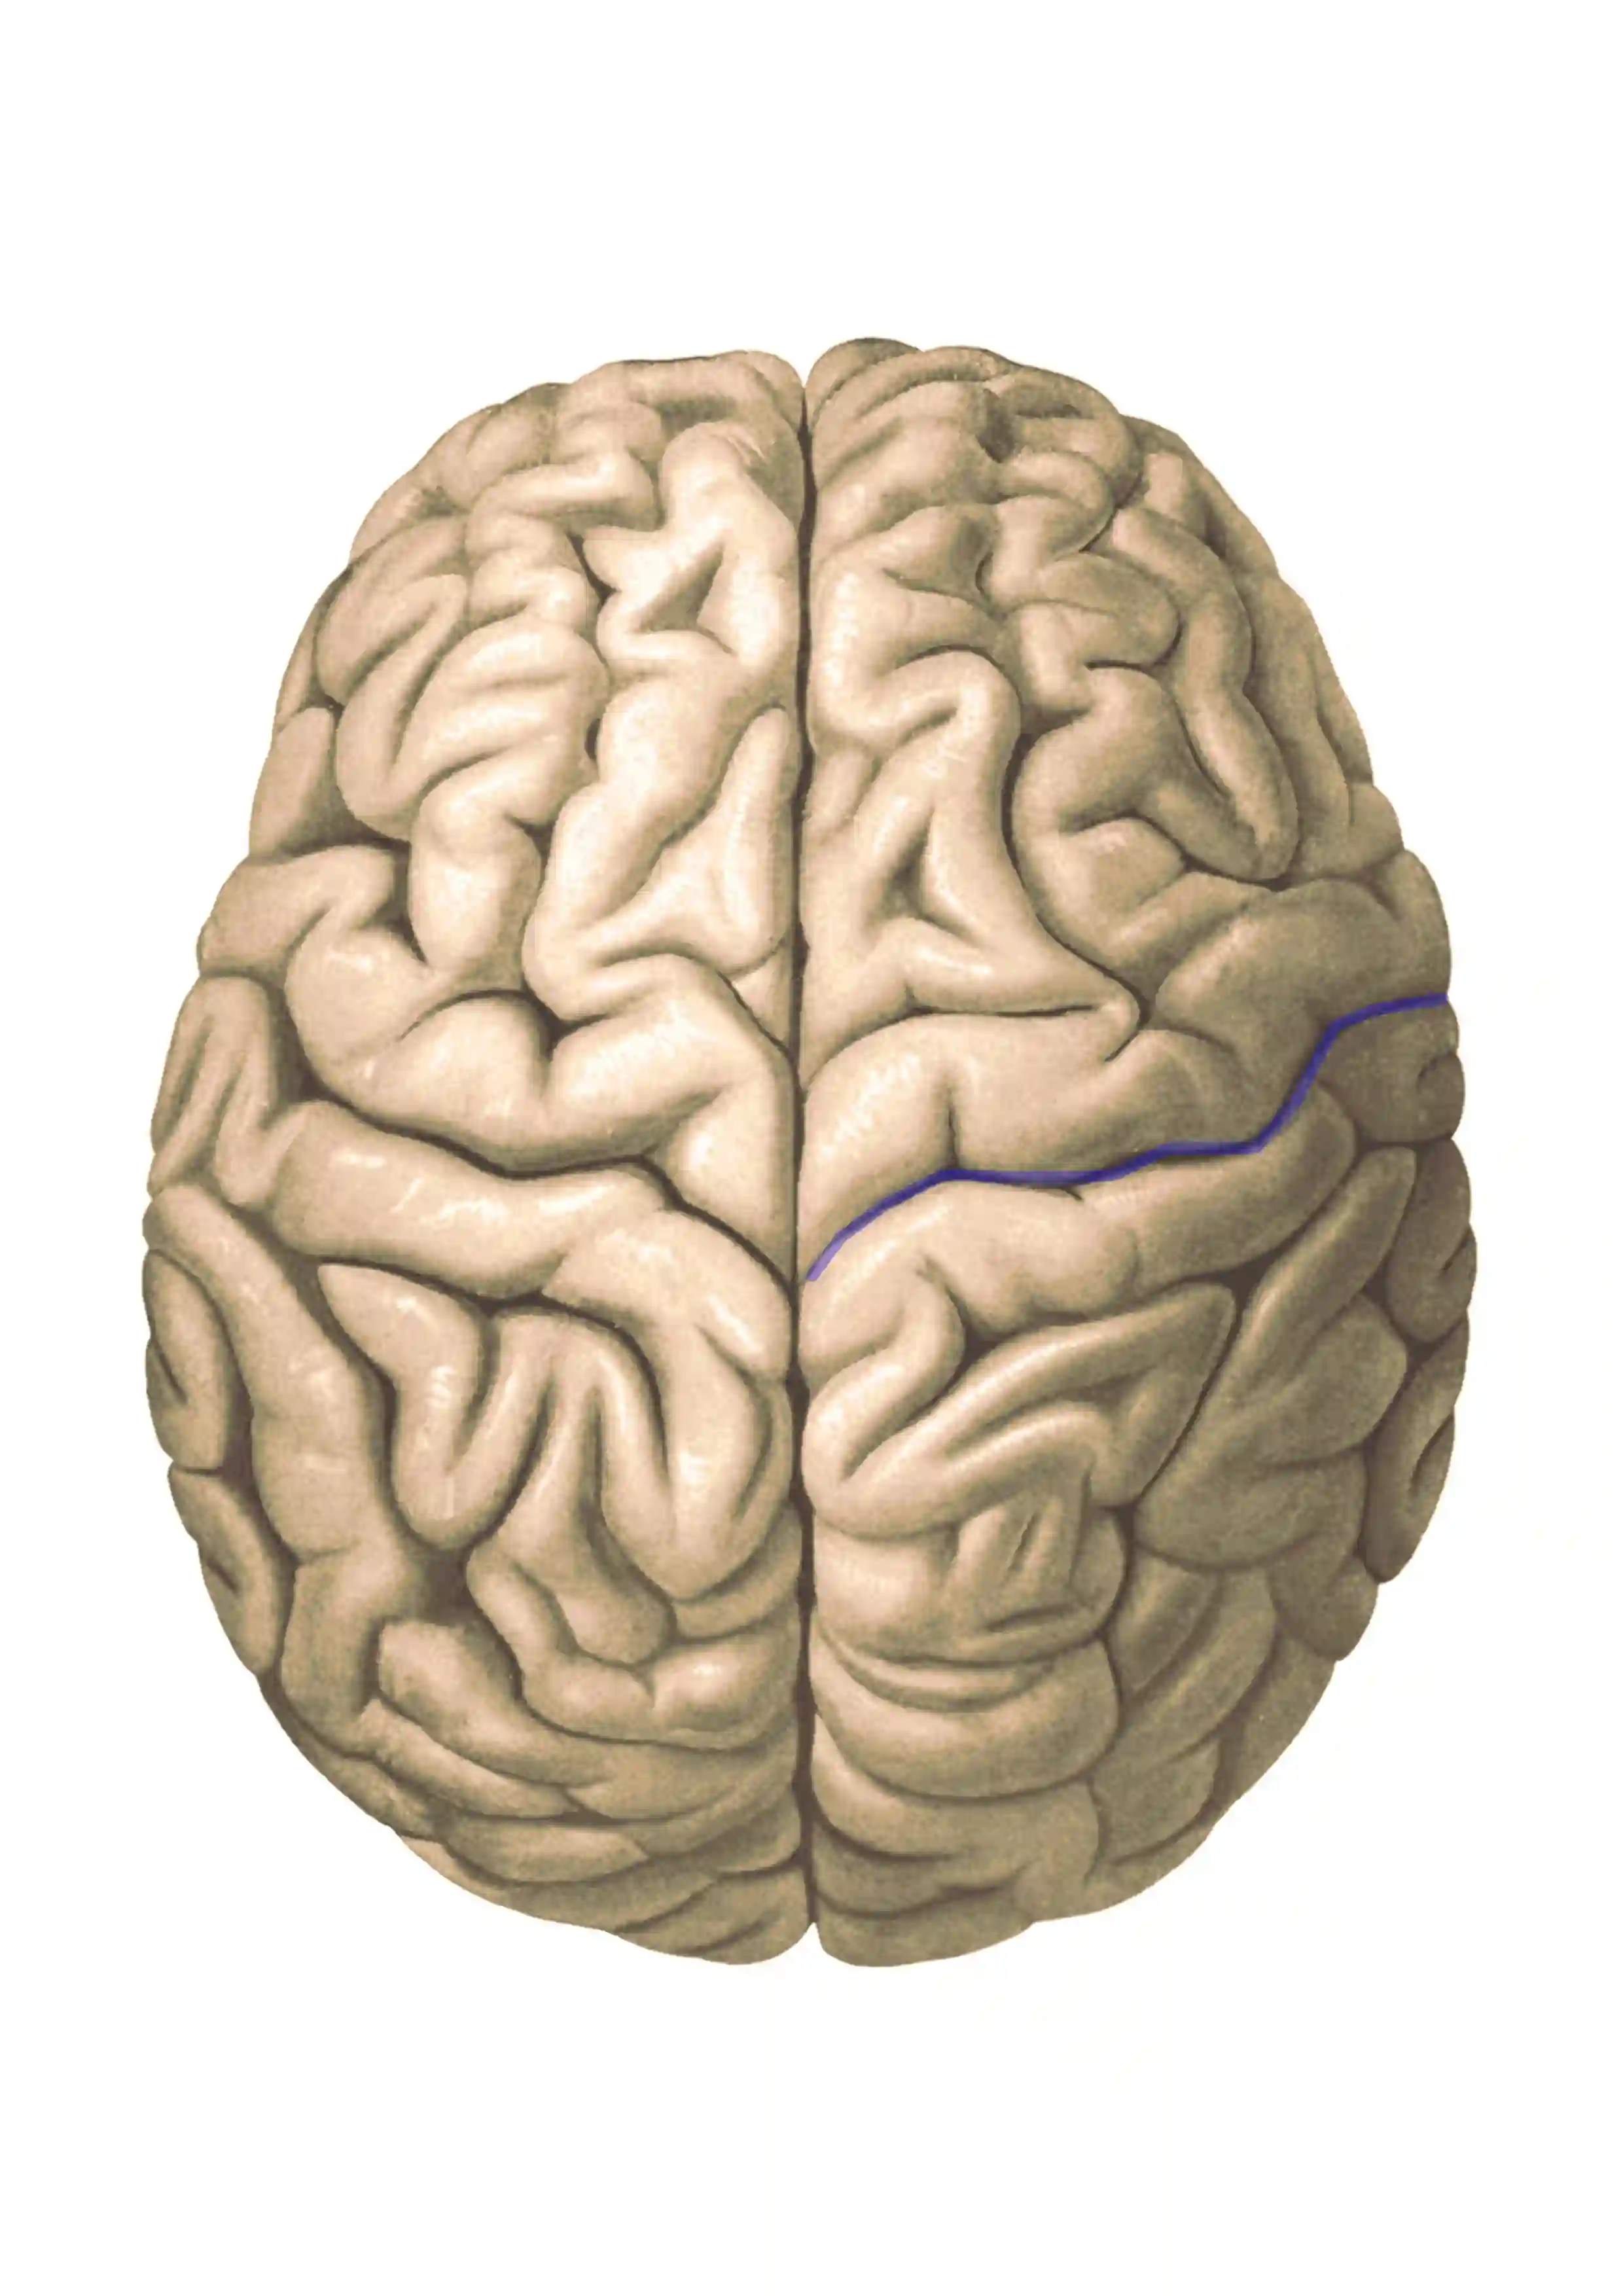

Abbildung

Sulcus centralis

Abbildung des Sulcus centralis (blau markiert) in einer anatomischen Zeichnung von Sobotta (Figure 628).